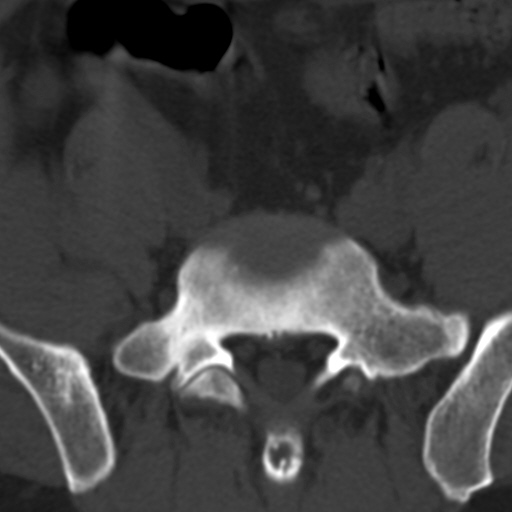

标题: CT4742:椎弓病变,请各位会诊。

男性,37岁,体检发现。

椎弓棘突形态、大小正常,左右椎板及棘突交界区骨质缺损,考虑良性病变(血管瘤可能)。

椎弓棘突形态、大小正常,左右椎板及棘突交界区骨质缺损,边缘清楚,后分见两个小点状高密影,考虑良性病变[血管瘤、成骨细胞瘤,骨纤,骨囊肿]

左右椎板及棘突交界区骨质缺损,周围未见软组织肿块及肿胀,考虑良性病变(血管瘤可能)。

破坏区呈彭胀性 切有硬化缘 考虑良性占位  囊肿可能性大